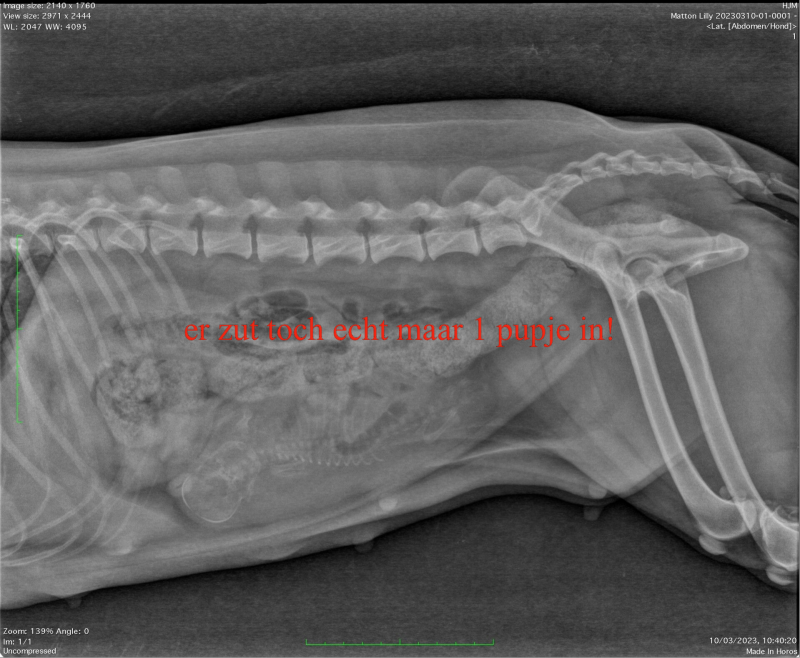

10 maart, we hebben gelijk een foto gemaakt toen we toch de nietjes moesten verwijderen. Helaas is er maar 1 pup in stuitligging te zien. Laten we hopen dat de bevalling toch spontaan begint en we zonder keizersnede onze pup mogen verwelkomen!